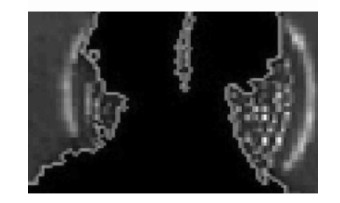

从图中脑室CT图像分割结果(图 4)来看,Chan-Vese模型分割方法在灰度值变化剧烈时能量最小化效果显著,能够准确判断并继续演化,但是在灰度变化缓和时,能量函数对停止收敛的判断存在很大的不确定性,导致最终分割过早结束,产生不完全分割的结果。而笔者提出的方法则大大改善了原方法这一缺陷,在腰部及右下尖锐边缘处很好地跟踪捕捉到了目标边缘,扩大了分割结果的有效面积。另一方面,Chan-Vese模型的最优化结果需要对整张图像素点的遍历,导致算法需要花费大量时间。笔者引入阈值算法预分割,阈值分割初步地排除掉大部分干扰算法分割,缩小算法遍历定义域,在进一步的Chan-Vese模型分割时大大减少了遍历的像素点,再结合尺度变化后保证了水平集的演化速度,最终达到了节省大量分割时间的目的。从图 5中可看出改进C-V算法的有效面积明显增大,图 6反映了改进C-V算法对复杂边缘良好的追踪。

|

图 4 两种算法对图像分割结果 |

|

图 5 局部分割效果放大后对比 (左为C-V模型,右为改进C-V模型) |

|

图 6 改进算法对尖锐边缘分割效果 |

在第一组实验中,C-V模型耗时2.66 s,改进算法耗时2.03 s,有效面积增大率为3.5%;第二组实验中,C-V模型耗时3.87 s,改进算法耗时2.96 s,有效面积增大率为4.7%。实验表明:结合阈值算法的Chan-Vese模型图像分割方法提高了图像分割的准确性和快速性。